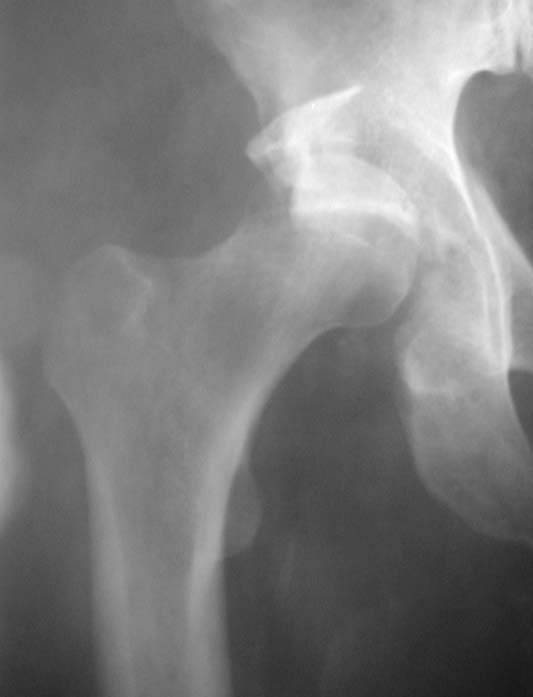

Уважаемые коллеги!Мужчина, 40 лет. Травма несколько месяцев назад. Получил закрытый вывих правого тазобедренного сустава и перелом вертлужной впадины (сним.1).Лечился скелетным вытяжением. Сейчас (сним.2) жалобы на боли, ограничение движений. Вопрос: тактика лечения (эндопротезирование и/или восстановительная операция, иное)?С уважением,А.В.Владзимирский

Вывих, похоже, вообще не был устранен. Или из-за дефекта заднего края сразу рецидивировал.

Для уточнения величины дефекта задней стенки и состояния головки необходима КТ. Если МРТ доступна, то и ее.

Если головка живая, прошло менее 2 мес., то мы бы наложили аппарат, стянули бедро дистально за неделю, потом открыто выполнили бы вправление с реконструкцией заднего края, скорее всего с аутопластикой, и фиксировали мостовидной пластиной (чтобы не мешало в дальнейшем эндопротезу).

Если срок больше, головка плохая, и дефект незначительный, то сразу эндопротезирование. Если значительный дефект и будут сложности, то

предусмотреть усложнение операции эндопротезирования из-за той или иной реконструкции впадины (аутопластика, остеосинтез края, укрепляющее кольцо).